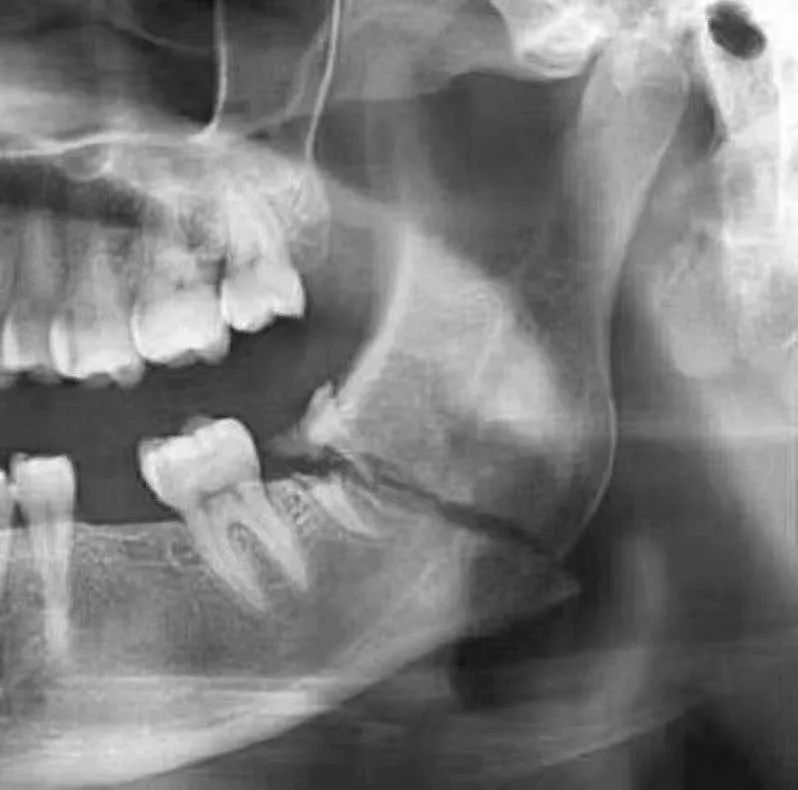

例如,當拔低頜智慧齒嘅時候,只憑口內檢查唔到佢嘅神經管位置

線片x線片唔止可以明白牙齒本身嘅病變情況,還可以明白牙根下有冇囊腫、周圍骨頭有冇吸收以及牙槽骨入面有冇埋伏牙、多生牙等。依據X線片綜合分析,可以提高齒科醫生診斷治療牙齒嘅準確性同成功率。

由於牙齒下部隱藏喺牙床骨入面,口腔醫生要瞭解牙齒嘅整體情況就需要拍攝全景片;而要了解各個牙根同埋周圍嘅變化,則選擇拍攝小牙片。

醫生想判斷牙床骨係咪適合種植條件,或者了解埋伏嘅阻生齒嘅三維位置同埋其他頜骨內嘅病變組織嘅形態同大小時,就需要進一步影相 CBCT 。